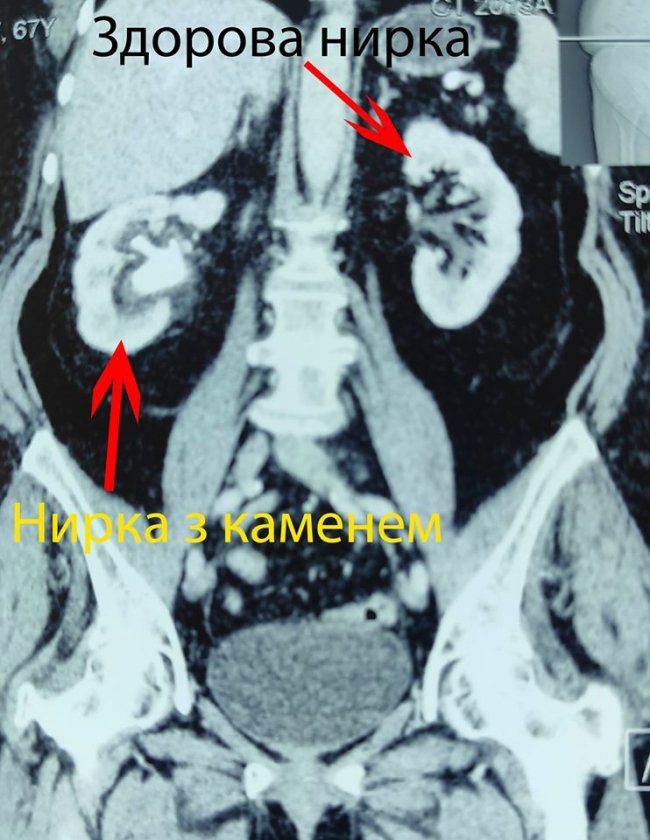

У волинській лікарні пацієнту видалили камінь, що «окупував» всю нирку. ФОТО

Відновлення планових оперативних втручань в Центрі ендоурології Ковельського МТМО почалося з непростої операції - видалення кораловидного каменя.

За його словами, пацієнту видалили камінь із правої нирки через єдиний мініатюрний прокол на шкірі.

"Камінь займав всю порожнину нирки. Під час операції конкремент поступово вдалося видалити повністю", - відзначив уролог.

Нині пацієнт почуває себе задовільно і проходить післяопераційну реабілітацію.